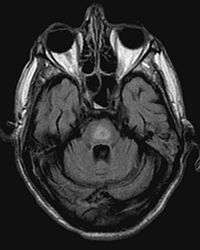

It can be difficult to identify using conventional imaging techniques. It presents more prominently on MRI than on CT, often taking several weeks after acute onset of symptoms before it becomes identifiable. Imaging by MRI demonstrates an area of high signal return on T2 weighted images.